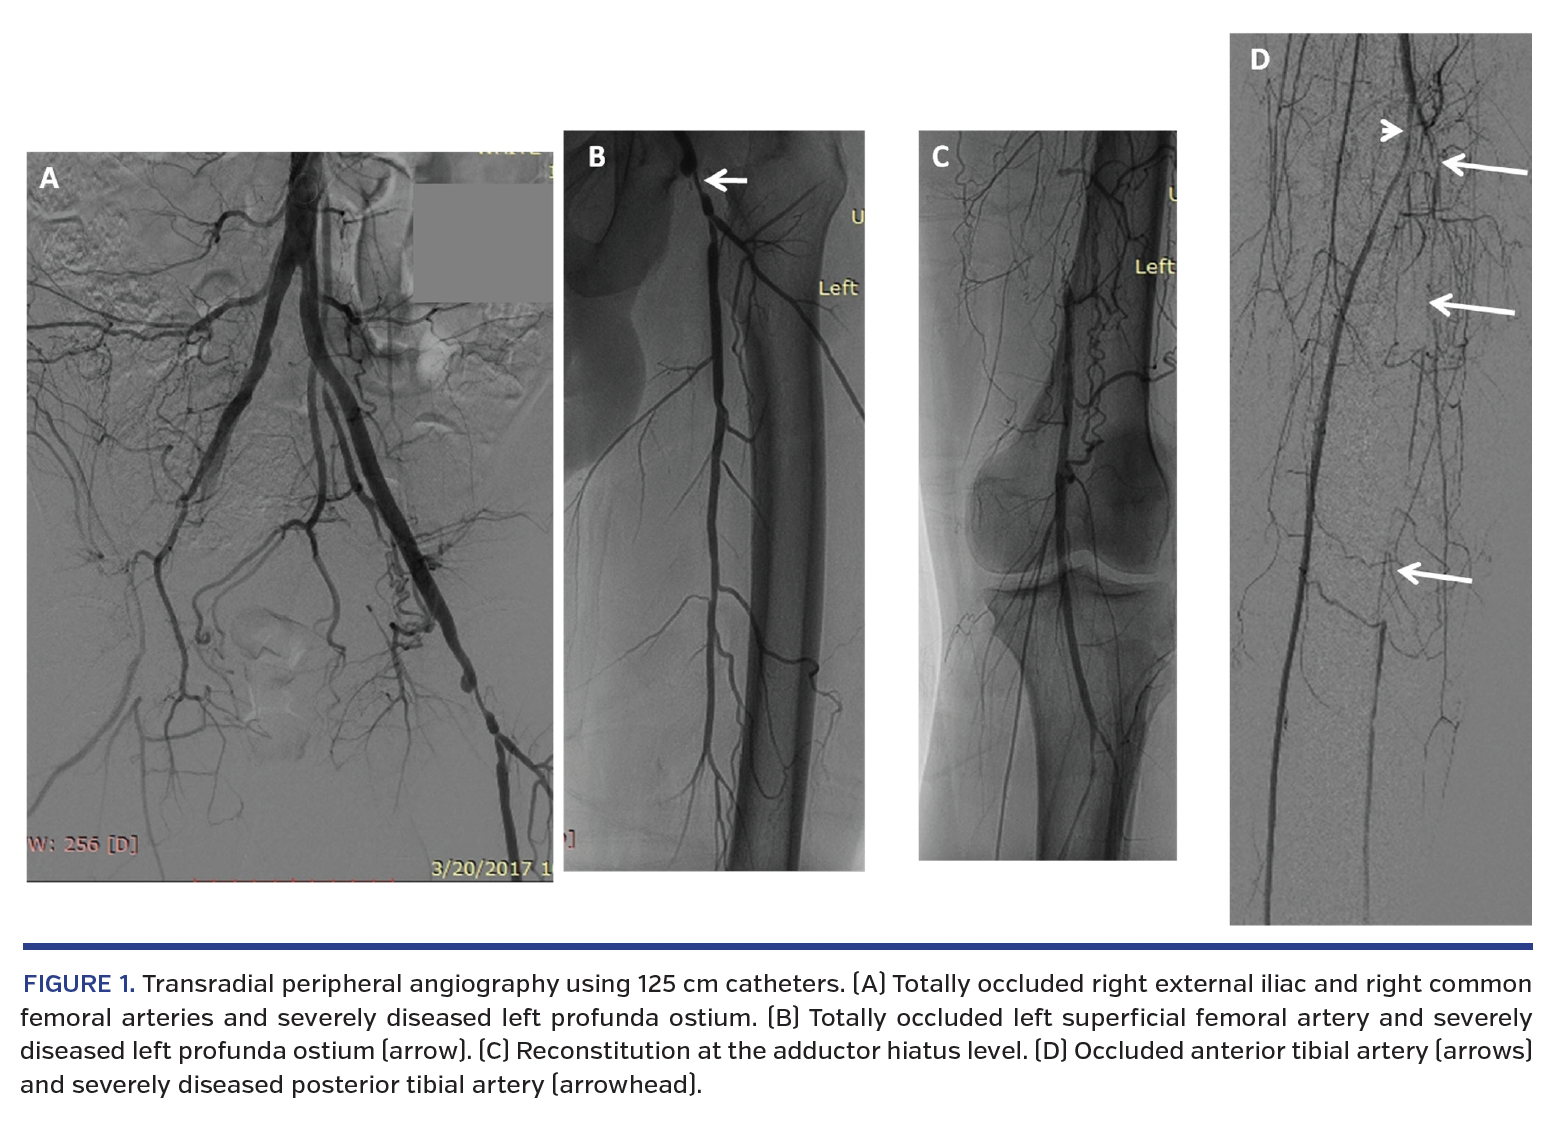

A 45-year-old, 172 cm-tall, male smoker presented with extensive non-healing ulcerations of the left leg and left second toe (ankle-brachial index, 0.1). His arterial access options were limited; the right common femoral artery was occluded and the left forearm had contractures from a prior stroke. As a result, the following stepwise revascularization strategy was adopted:

1. The right radial artery was accessed and selective left femoral angiography was performed via 6 Fr, 125 cm multipurpose guiding catheter. Extensive femoral and infrapopliteal disease was demonstrated (Figure 1).